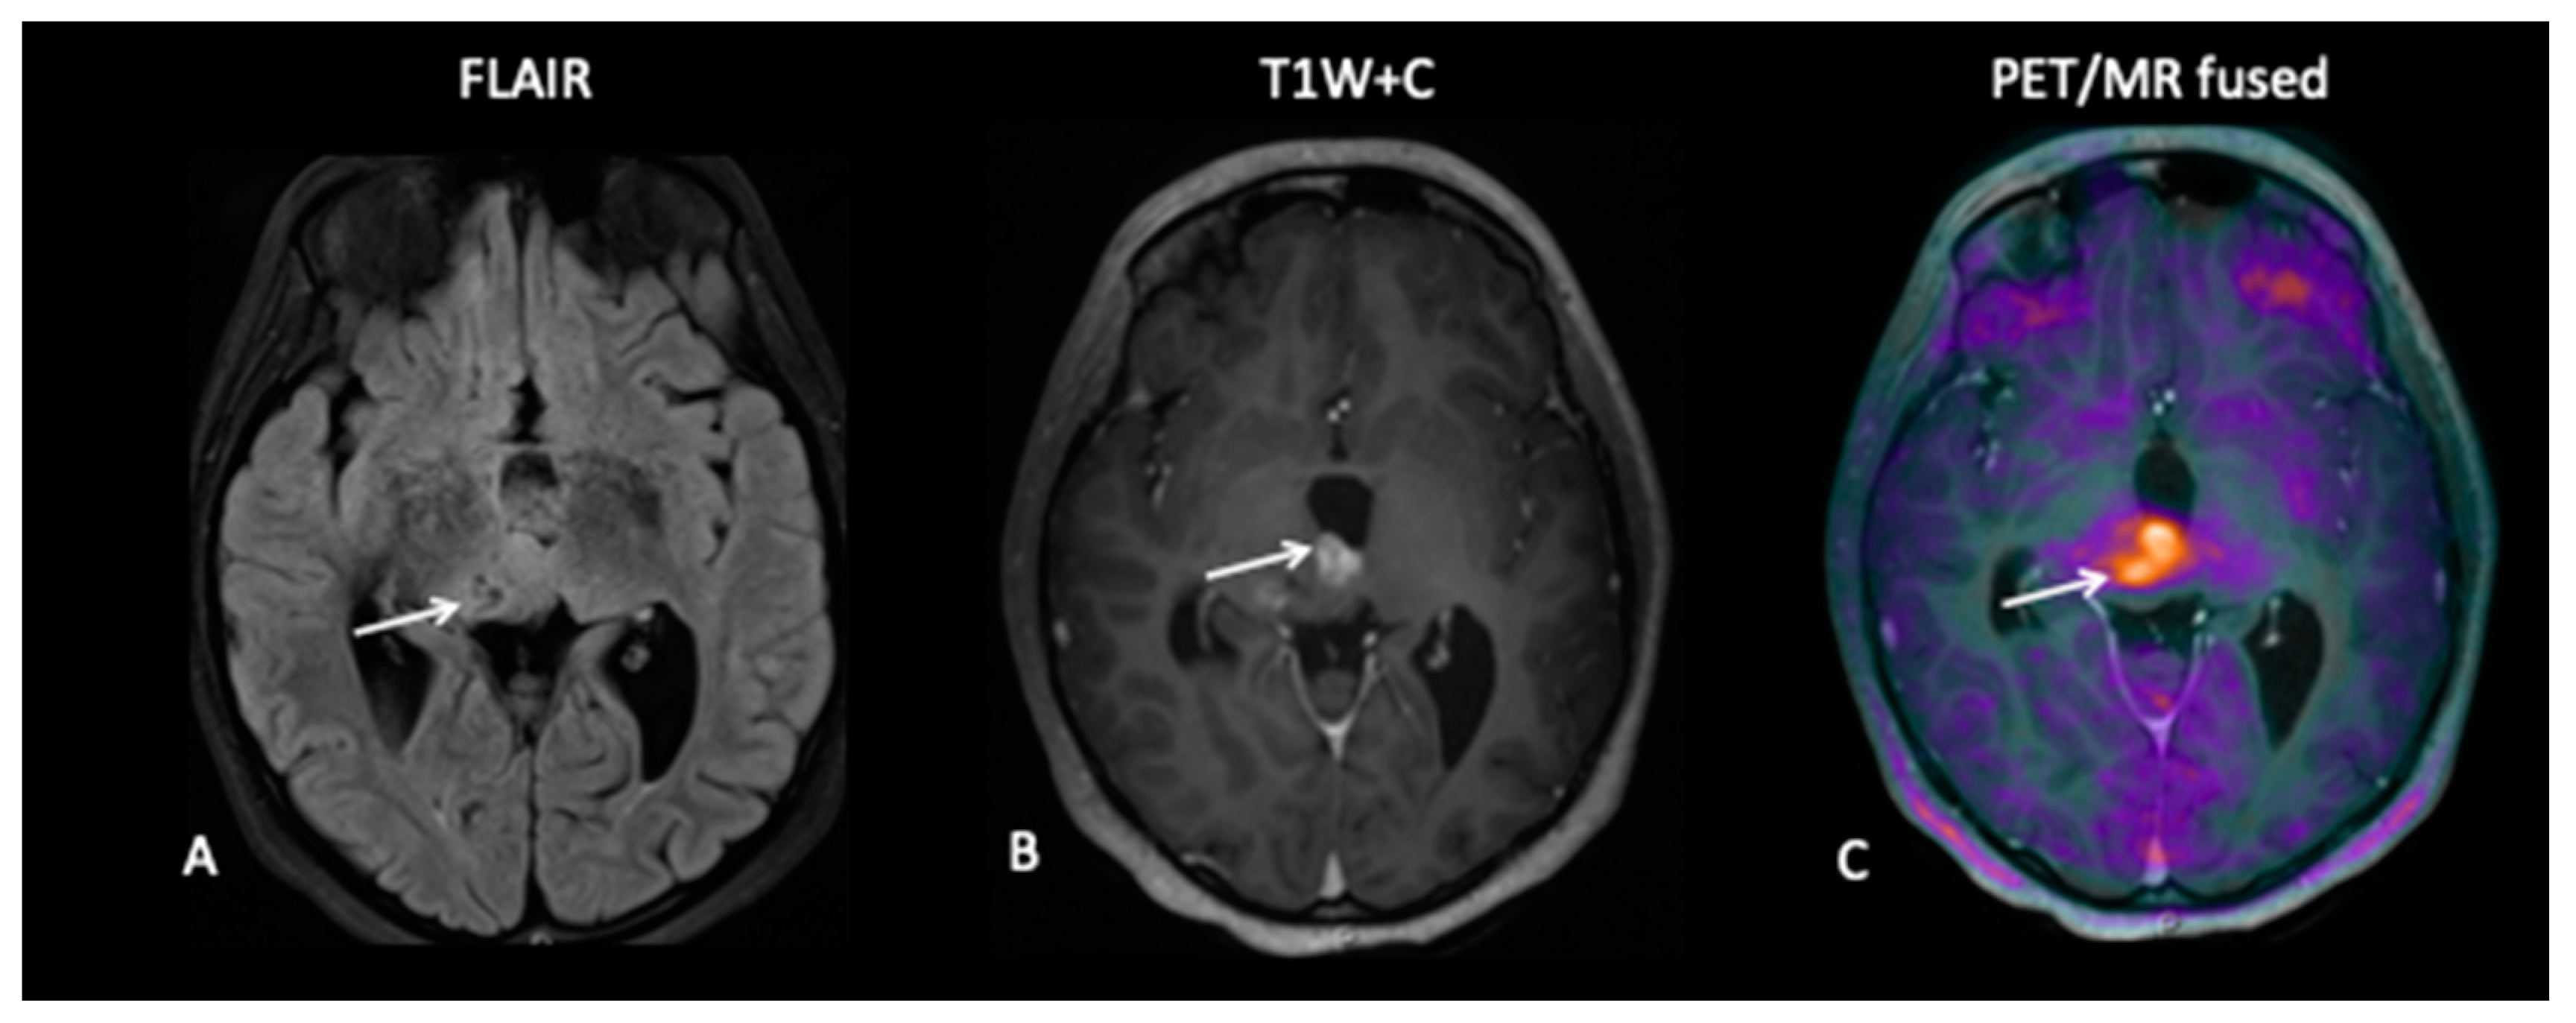

A 10-year-old presented with low-grade glioma with a background of NF1 (neurofibromatosis type 1). A mid treatment MRI scan following disease progression showed enlargement of an enhancing lesion in the right cerebellar hemisphere, but the patient was well and clinically stable, and the radiological changes were thought to reflect pseudoprogression. An FDOPA PET–MRI showed increased tracer activity in the enhancing lesion along with a second FDOPA avid lesion in the right subthalamic region, consistent with metabolically active disease (Figure 9).

Figure 9.

A mid-treatment scan demonstrates an enlarging right cerebellar hemisphere lesion (A,B) thought to reflect pseudoprogression, but FDOPA demonstrates increased uptake (C) and identifies a further lesion in the midbrain (F) not obviously apparent on the T2W image (D) or T1W post-contrast image (E), which is consistent with multifocal tumour progression.

- Patient 7: Treatment Response

A 7-year-old female presented with tremors and an upward gaze palsy. A MRI scan showed a large tectal plate tumour involving the right thalamus causing secondary hydrocephalus.

She had a ventriculo-peritoneal (VP) shunt inserted for CSF diversion, but 4 years later following tumour progression, she underwent a biopsy which confirmed low-grade glioma. FDOPA showed intense uptake in both the enhancing and non-enhancing components of the tumour (Figure 10), following which the patient was referred for proton beam treatment PBT]. Post PBT FDOPA at 8 weeks showed complete metabolic response.

Figure 10.

The MRI study demonstrates a large area of signal abnormality in the right thalamus (A) associated with a medial enhancing nodule (B). However, FDOPA demonstrates increased uptake in the non-enhancing component in addition to the enhancing component (C), confirming metabolically active non-enhancing disease in the right thalamus.